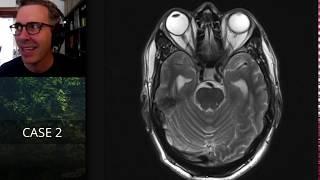

This nephrologist makes GN easy for exams: free tutes at https://tutorials.kristeenbarker.com

Tutorials by Kristeen Barker

243

809

5 месяцев назад